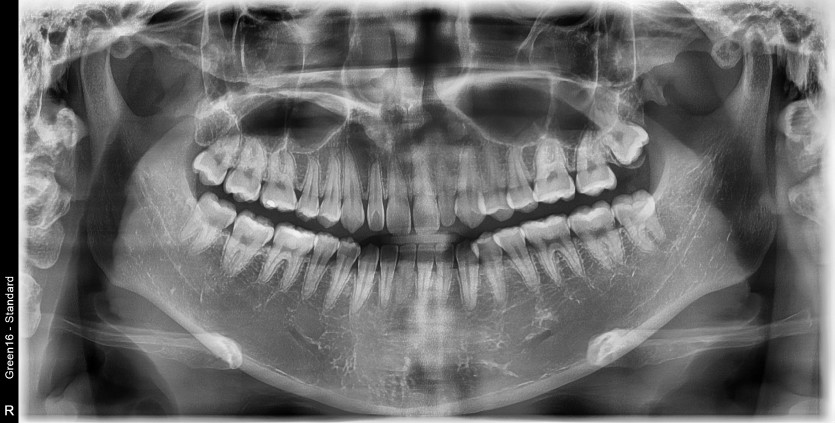

#38 사랑니 발치

구강 외과 전문의가 당일 발치했습니다.